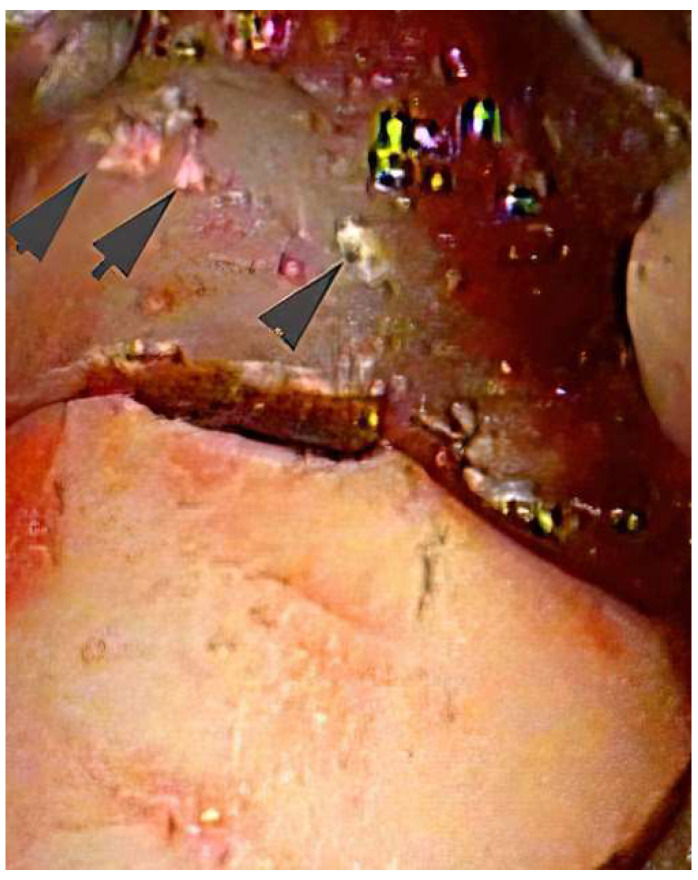

Results: The published literature supports that calculus is a major risk factor for periodontal inflammation. Recent studies indicate that the pathologic risk of calculus goes beyond the retention of biofilm and may represent a different pathophysiologic pathway for periodontal disease separate from the direct action of biofilm. The inadequate removal of calculus is a factor in the failure of periodontal therapy.

Conclusions: The inadequate removal of calculus plays an important role in the frequent failure of non-surgical periodontal therapy to eliminate inflammation.